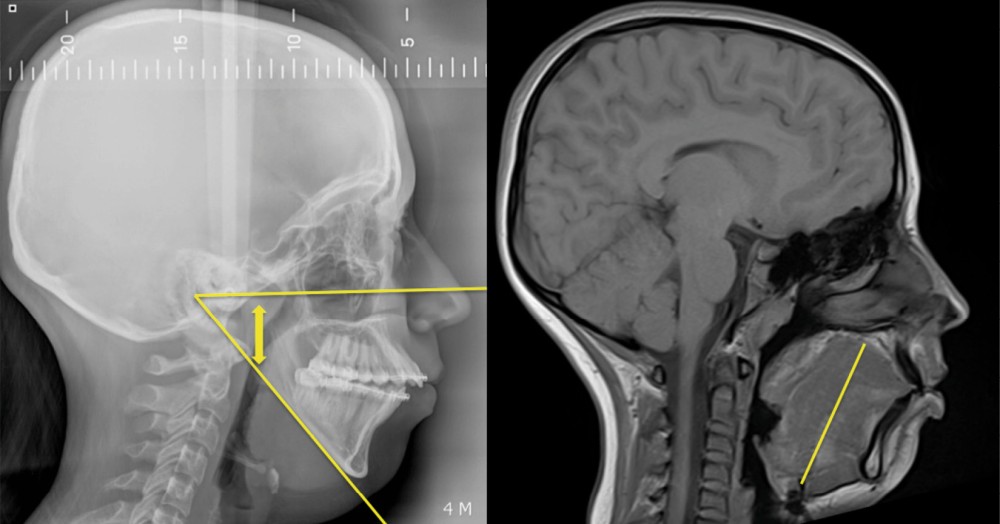

L’étroitesse squelettique peut également être impliquée (rétromandibulie, hyperdivergence, endognathie) [1] (fig. 1-4).

Plusieurs approches chirurgicales ont été décrites : les chirurgies des tissus mous visant la désobstruction pharyngée, les chirurgies squelettiques destinées à élargir le calibre pharyngé et, plus récemment, les interventions visant à augmenter le tonus musculaire lingual par stimulation du nerf hypoglosse (fig. 5).